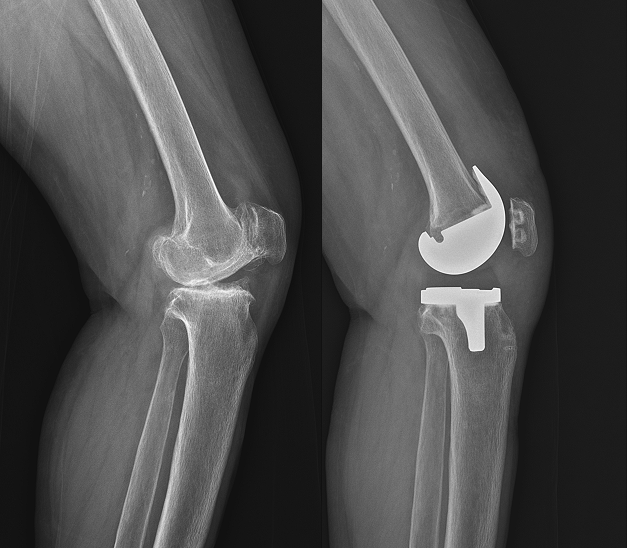

인공관절치환술

기능 회복

통증 완화